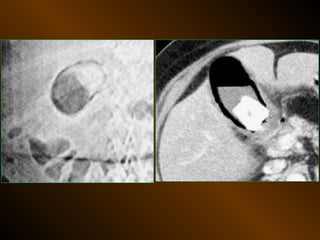

TỤ DỊCH KHU TRÚ

• X QUANG QUY ƯỚC

– Tụ dịch ? – khối u ?

• SIÊU ÂM

– Phản âm, chất chứa, vỏ bọc ?

• X QUANG CẮT LỚP ĐIỆN TOÁN

– Mật độ, bắt cản quang ?

TỤ DỊCH NGOÀI PHÚC MẠC

TỤ KHÍ NGOÀI PHÚC MẠC

• Nguyên nhân :

– Thủng tạng rỗng

– Áp xe tạo khí

• XQCLĐT

TỤ KHÍ NGOÀIPHÚC MẠC • Nguyên nhân : – Thủng tạng rỗng – Áp xe tạo khí • X quang quy ước • Siêu âm • XQCLĐT